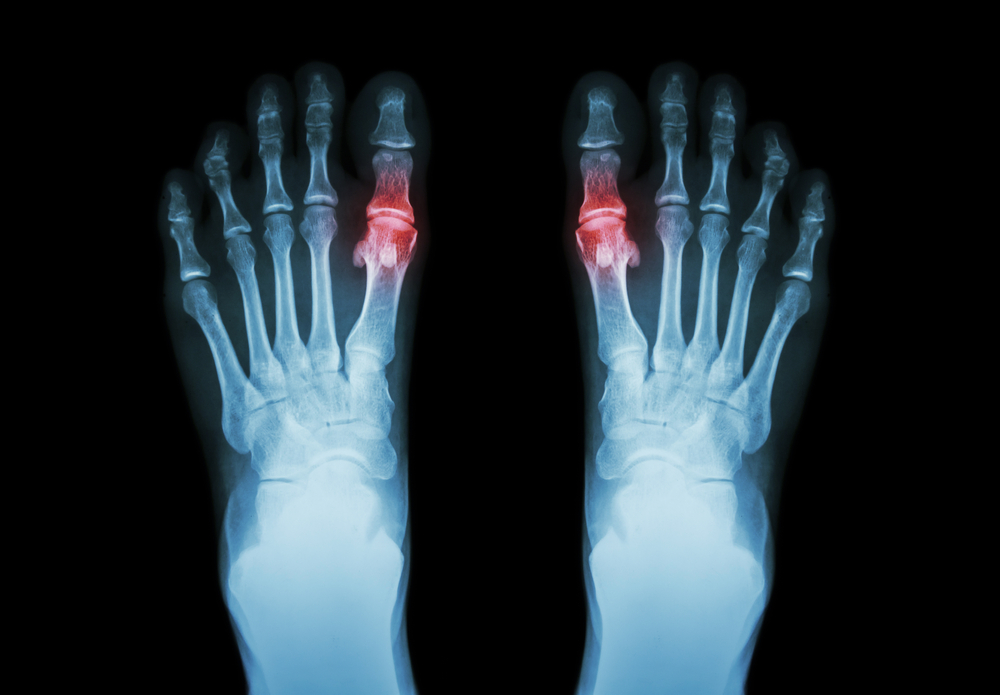

Подагра, как хроническое заболевание, характеризуется различными клиническими проявлениями, которые могут варьироваться от острых приступов до бессимптомного течения. Основным проявлением подагры является острый артрит, который чаще всего затрагивает один сустав, наиболее часто — большой палец ноги. Однако, в зависимости от стадии заболевания, могут быть вовлечены и другие суставы, такие как коленные, голеностопные, локтевые и кистевые.

Острый приступ подагры обычно начинается внезапно, часто ночью, и сопровождается интенсивной болью, отеком, покраснением и повышением температуры в области пораженного сустава. Боль может быть настолько сильной, что даже легкое прикосновение к суставу вызывает дискомфорт. Важно отметить, что приступы могут повторяться с различной частотой и продолжительностью, и со временем могут становиться более продолжительными и менее предсказуемыми.

Инструментальные методы, такие как рентгенография, могут помочь в исключении других заболеваний суставов и выявлении возможных изменений, связанных с подагрой, таких как эрозии или отложения кристаллов. В некоторых случаях может быть проведена ультразвуковая диагностика, которая позволяет визуализировать отложения кристаллов мочевой кислоты в суставной жидкости.